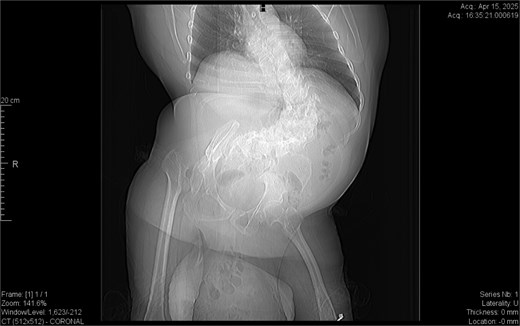

From the provided coronal CT image (Fig. 1), the following findings are noted: The spinal curvature is prominently right-convex in the lumbar region, indicating a dextroscoliosis with marked rotation of vertebral bodies, causing asymmetrical displacement of the retroperitoneal organs. The curvature shortens the abdominal cavity vertically on the left side, while expanding the retroperitoneal volume on the right. The right femoral head is elevated and laterally displaced, consistent with developmental dysplasia of the hip. There is flattening of the acetabulum and apparent false articulation with the iliac wing. These findings suggest chronic alteration of pelvic symmetry with pelvic tilt and subsequent uneven distribution of abdominal and intra-pelvic pressure. The combined effects of spinal curvature and pelvic deformity create an aberrant vector of force and organ positioning, contributing to the downward displacement of the pancreas and duodenum.

Dextroscoliosis with marked rotation of vertebral bodies, displaced right femoral head and giant inguinal hernia.